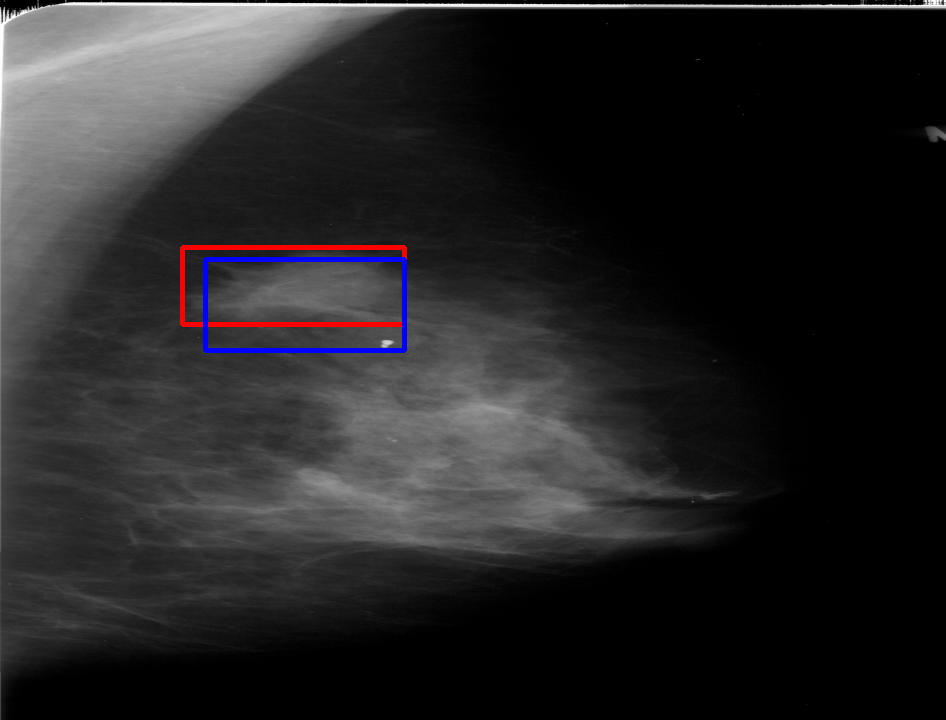

UDA has been extensively studied in case of natural images, utilizing techniques such as adversarial learning [21],pseudo-label training [6, 21, 40], image-to-image translation [40], graph reasoning [20], and adaptive mean Teacher training [6], improving domain adaptation efficiency of object detectors. Recently multiple works focused on using Mask autoencoders (MAE) methods in large-scale pretraining for vision models, involving masking parts of input and reconstructing them [12, 33]. However, these approaches overlook domain shifts. Alternatively, widespread utilization of Teacher-Student models, wherein a Teacher provides pseudo-labels for target domain (unlabeled images) to supervise a Student model, leads to notable adaptation improvements [40, 43]. However, these techniques face the challenge of incorrect predictions and excessive false positives per image due to low-quality pseudo-labels, particularly for medical imaging problems. Pseudo-labels are filtered from the Teacher model’s outputs based on the confidence score threshold. Selecting numerous pseudo-labels with low thresholds leads to inclusion of incorrect predictions, and compromising performance. Conversely, higher thresholds yield a limited number of pseudo-boxes, resulting in sub-optimal supervision. Existing Teacher-Student models often produce pseudo-labels riddled with errors and false positives, as illustrated in Fig. 1(a) and Fig. 1(b). Though [21, 40, 43] utilize techniques like adversarial alignment, weak-strong augmentation, and selective retraining of Student model to minimize the false positives in pseudo-labels, these approaches fail on medical images.

Contributions of this work. We note that screening mammography inherently differs from natural images, with breast abnormalities such as masses, asymmetries, and micro-calcifications, typically much smaller in comparison to the salient objects present in natural images, emphasizing the need for approaches specific to this problem. To address these issues, we make following contributions in this work: (1) We introduce D-MASTER, a transformer-based Domain-invariant Mask Annealed Student Teacher Autoencoder Framework for cross-domain breast cancer detection from mammograms (BCDM), integrating a novel mask-annealing technique and adaptive confidence refinement module. Unlike pretraining with mask autoencoders (MAEs) [12], leveraging massive datasets for training and then fine-tuning on smaller datasets, we present a novel learnable masking technique for the MAE branch that generates masks of different complexities, which are reconstructed by the DefDETR [44] encoder and decoder. Our approach, as a self-supervised task on target images, enables the encoder to acquire domain-invariant features and learn better target representations as shown in Fig. 1(c). (2) In Teacher-Student model, since the pseudo-label noise generated by the Teacher affects the Student model severely, we propose an adaptive confidence refinement module that progressively restricts the confidence metric for pseudo-label filtering. During the initial adaptation phase, soft confidence is applied allowing more pseudo-labels to learn better target representations. Subsequently, as confidence gradually increases, the focus shifts towards enhancing detection accuracy by prioritizing more reliable pseudo-labels. (3) We release a bounding box annotated subset of 1000 mammograms from the RSNA Breast Screening Dataset (referred to as RSNA-BSD1K) to support further research in BCDM. (4) We setup a new state-of-the-art (SOTA) in detection accuracy for UDA settings. We report a sensitivity of 0.74 on INBreast [25] and 0.51 on DDSM [18] at 0.3 FPI, compared to 0.61 and 0.44 using current SOTA respectively. Significant performance gains are also observed on our in-house and RSNA-BSD1K datasets.